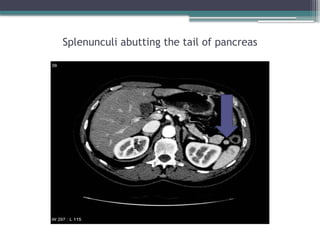

SPLENUNCULI (anatomy, physiology, pathology and management) | PPTX